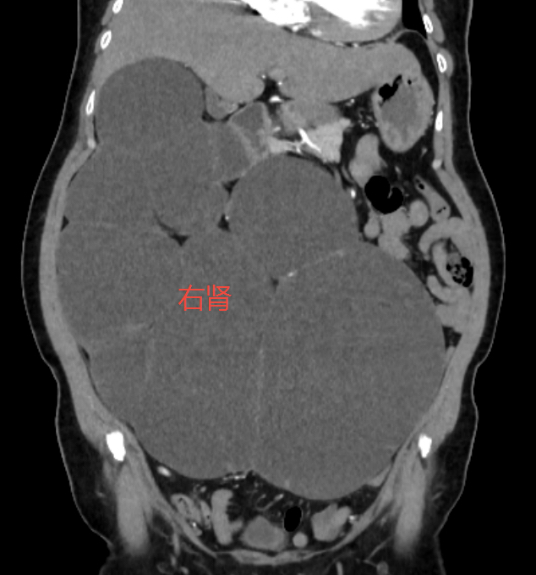

春节回家,长年在深圳打拼的小李(化名)看到自己60岁的老母亲比以往胖了不少,尤其是肚子,胖了两圈还不止,说是“怀胎十月”都不为过,可老人家说并没有感到不舒服,偶尔有点腰酸腰胀,忍一忍也就过去了。小李听后不放心,过完春节便马上带母亲来到大医院检查,结果发现老母亲的肚子居然是被右肾给填满了,此时的右肾已经像气球一样被吹到了将近40cm,并且里面充满尿液,功能也已丧失,而罪魁祸首竟是一颗“潜伏”在输尿管内的仅有0.8cm的结石。这颗从未引发疼痛的结石,像一道闸门,让她的肾脏在不知不觉中被积水“淹没”。

小李母亲的影像结果显示,她的右肾皮质已薄如纸片,且无血流信号——这正是肾脏“死亡”的表现。